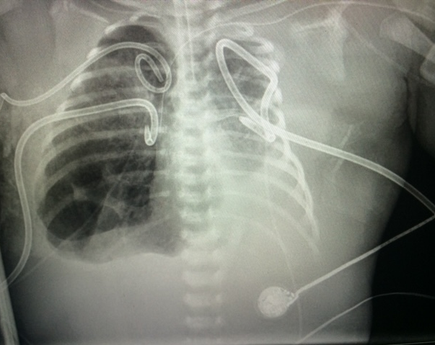

When baby Khovny was born, the joy of her birth was tinged with fear: She was in the Neonatal Intensive Care Unit at Oregon Health & Science University Doernbecher Children’s Hospital, being urgently treated for hydrops, a life-threatening condition in which fluids accumulate in a fetus’s body.

The experience was particularly scary for her parents, Shabri and Kevin Vignery, who had lost their baby Ryan to the same condition a year earlier. He wasn’t treated until Shabri was rushed to OHSU Doernbecher to deliver him.

Khovny’s hydrops was identified early, and the Vignerys, of Keizer, were referred to OHSU Doernbecher, whose fetal care program provides the most complex prenatal care between Seattle and San Francisco. OHSU physicians performed various in-utero, or in the uterus, procedures to help remove excess fluids, until they delivered the baby by cesarean section at 33 weeks.

Now, Khovny is a vibrant, healthy 5-year-old who likes to dance and loves her 10-year-old brother, Evan. She’s named after the physicians who helped care for her and Ryan: Stephanie Dukhovny, M.D., associate professor of obstetrics and gynecology in the OHSU School of Medicine and director of the OHSU Doernbecher Children’s Hospital Fetal Care Program; and her husband, Dmitry Dukhovny, M.D., M.P.H., a neonatologist and associate professor of pediatrics (neonatology) in the OHSU School of Medicine.

The in-utero technology that helped successfully treat Khovny is only available in Oregon at the OHSU Doernbecher Fetal Care Program. Now, with two new surgeons, that program is expanding to provide even more complex, in-utero surgeries, becoming one of the most comprehensive fetal care centers in the Pacific Northwest — transformational for families who would otherwise have to travel out-of-state for treatment.

Topete, of Southwest Washington, was the first patient treated by the newly expanded fetal surgeon team. To treat her fetus’s hydrops in-utero, the team successfully placed a shunt to drain excess liquid, leading to a quick recovery once her baby girl was born. Now 12 weeks old, her baby is healthy and happy.